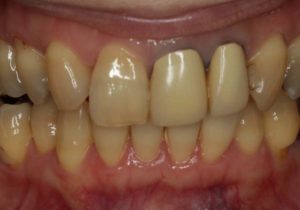

どのように変わったか、下の写真をご覧ください。

- 術前

- 術後